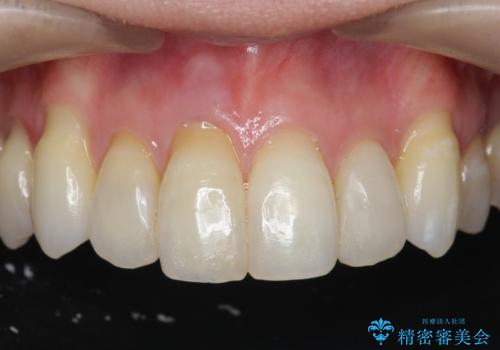

[ 再生治療・歯周外科・小矯正・セラミック補綴 ] 前歯の歯周病治療

担当医 大元洋佑